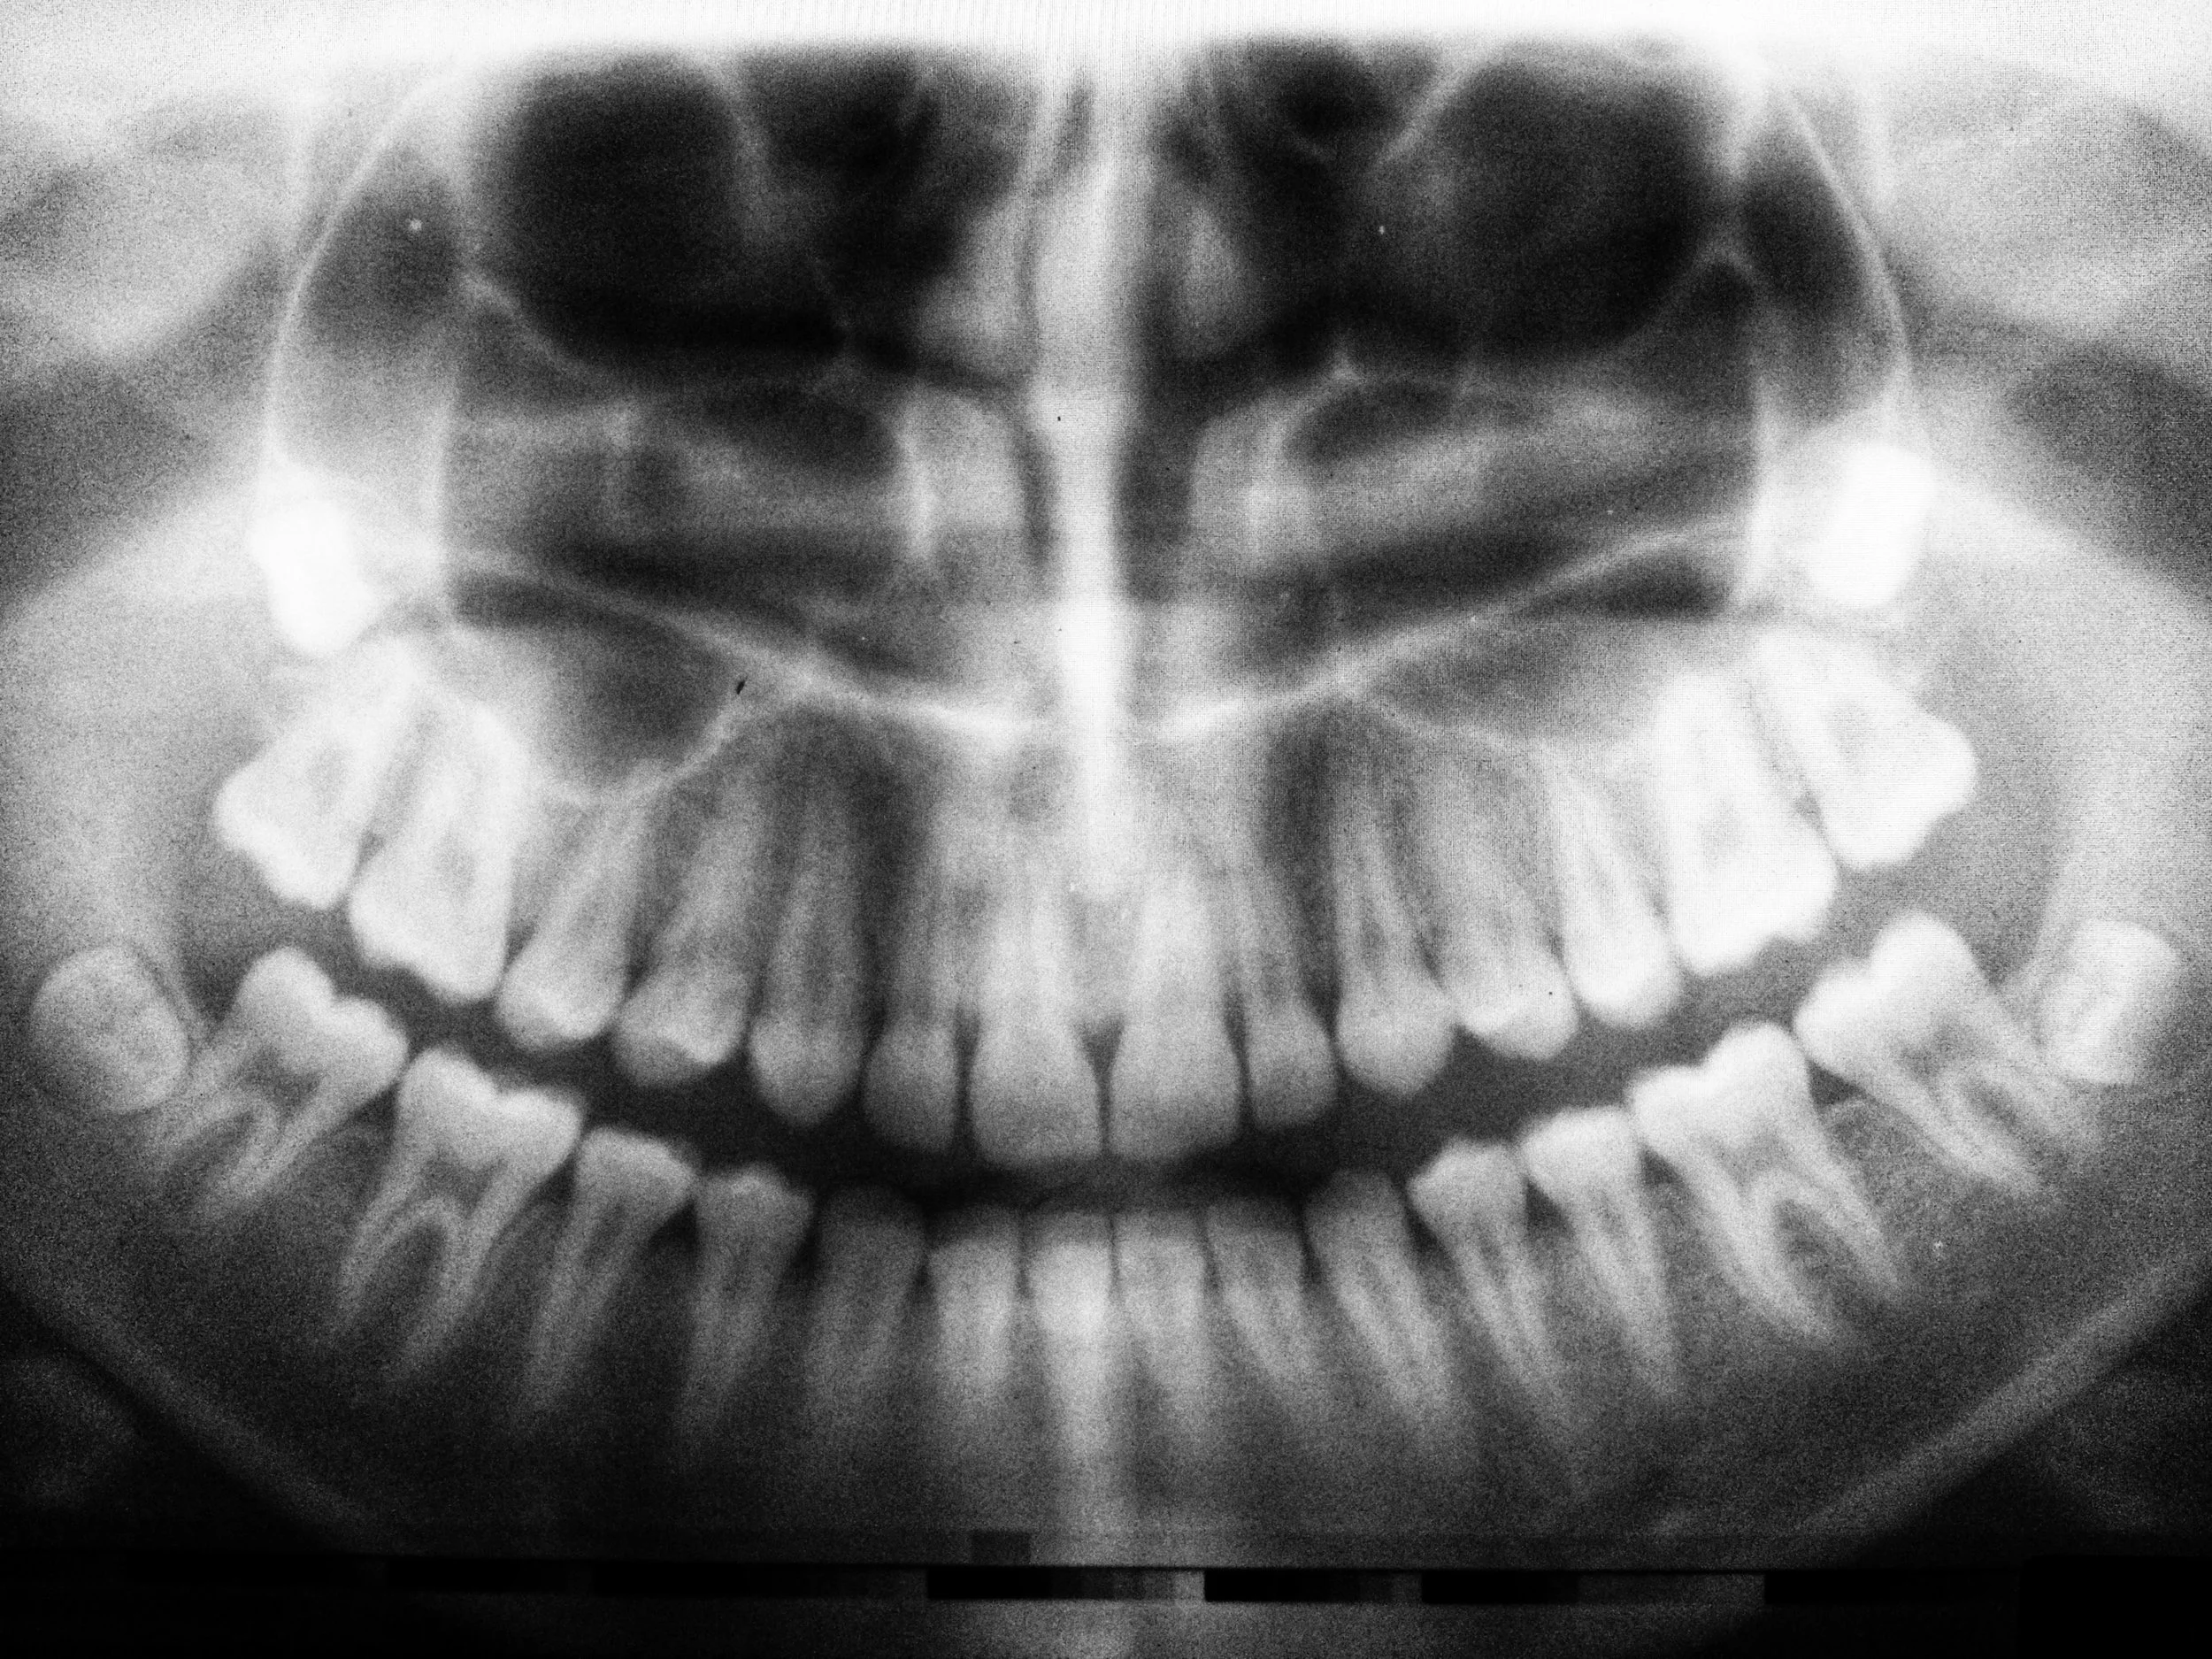

Comprehensive Evaluation – We take digital X-rays to assess the position of your wisdom teeth and determine if removal is necessary.